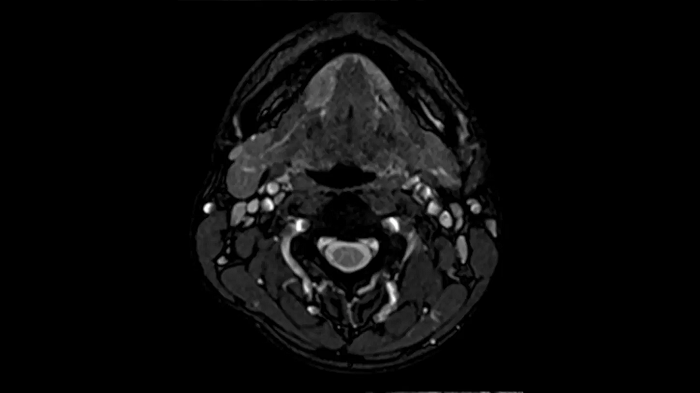

Neck

Excellent soft tissue contrast in the neck

An all-inclusive soft tissue investigation in the head with outstanding image quality for T1, T2, and diffusion contrast.

MAC-ID: 7aaaa0158. Image Credit: Siemens Healthineers